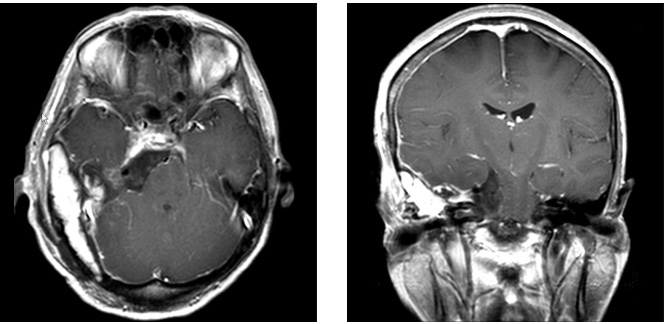

症例4は58歳。顔面の違和感で発見された小脳橋角部、テント髄膜腫である。三叉神経や外転神経、滑車神経などを巻き込む腫瘍。脳幹圧迫も強く症状は軽微であったが、腫瘍摘出を行った。後方複合錐体アプローチで一期的に神経を温存して腫瘍を摘出した。一時的に滑車神経麻痺による下方を見た時の副視が出現したが、改善している。

術前MRI 右側の脳神経を巻き込む腫瘍

神経を温存し腫瘍摘出